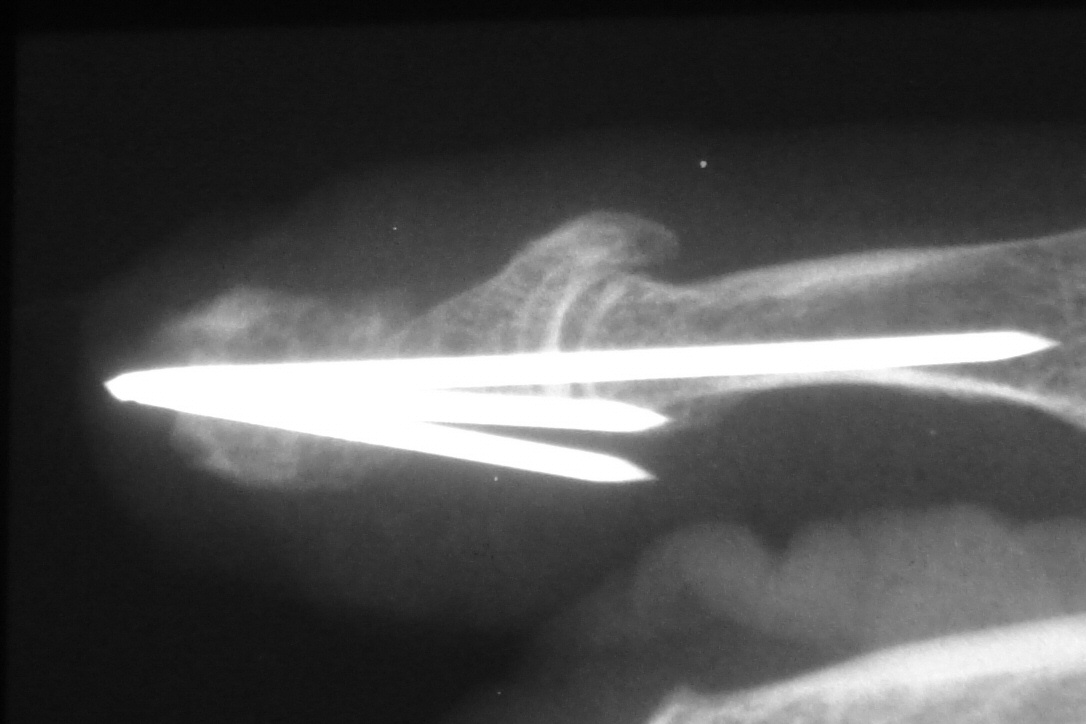

Following fingertip amputation, Hook nail deformity can result from loss of adequate supporting length of distal phalanx. This reduces the radius of curvature of the nail, and in extreme cases, the nail plate curves tightly over the end of the fingertip. One type of reconstruction involves lengthening the tip with a bone graft and skin flap, sometimes referred to as the "antenna procedure" because of the appearance of temporary pins protruding from the fingertip. One problem with this approach is that the distal bone graft may resorb slowly over the years that follow.

Xrays over this period: initial deformity, bone graft, and progressive bone graft loss over the course of years:

Image Image